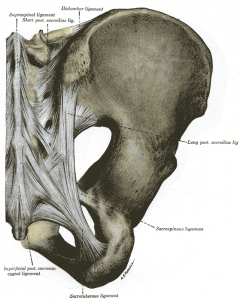

There is an important network of ligaments, which lie at the front and back of the pelvis. These ligaments are very important in Chiropractic, as weakness, tension, or trauma to the ligaments affects function of the joint. Between some of these ligaments passes muscle and nerves, which when compressed can affect local function.

The sacro-iliac joint (SIJ) consists of the sacrum (the large central triangular bone), and ilium (the large pelvis bone) on the outside. The sacro-iliac joint is important because it essentially forms the base of the spine – the next weight bearing joints above are the lumbar spine (low back), and sacro-iliac joint dysfunction can have effects upwards into the low back, mid back, and neck, and downwards into the knee and ankle.